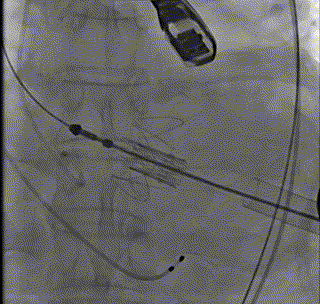

释放瓣膜

造影确定定位键位置与冠脉情况

再次造影无瓣周漏冠脉显影良好

经DSA透视下定位心尖位置,主刀团队于左腋前线第五肋间做一3.5cm水平切口,从穿刺心尖至退出植入系统、荷包打结仅耗时不到10分钟,整台手术耗时仅56分钟,再次造影及复做经食道心超见瓣膜位置满意,无明显瓣周漏及瓣内返流、左右冠脉显影良好,心尖切口荷包无出血,在做到微创、高效的同时,实现了满意的手术效果。